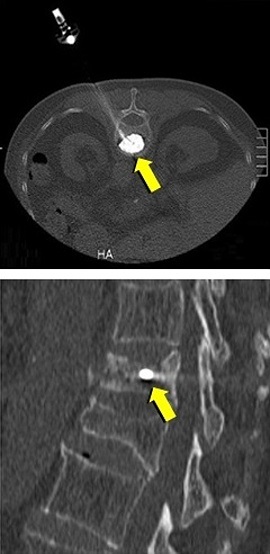

◆圧迫骨折/骨転移に対する経皮的椎体形成術(PVP)

経皮的椎体形成術(骨セメント)の実際

局所麻酔下で皮膚から椎体に針を刺し、骨セメントを注入することにより、椎体を内部

から固定する方法です。骨粗鬆症による圧迫骨折で痛みを伴うもの、椎体の腫瘍(癌の

転移など)による痛みを伴うものが適応となります。古い圧迫骨折による亀背や側弯が

あっても、痛みがないものや、症状のないものは治療の適応となりません。症状が軽度

であっても歩行時、起立時に痛みがあり、画像診断で治癒していない圧迫骨折がある場

合は治療の適応となります。術前の画像診断にはMRI検査が重要で、病的骨折、骨粗鬆

症性骨折、治癒していない骨折の診断に不可欠です。

治 療 前 セメント注入中 治 療 後

当院では各種の透視画像下に椎体形成術を行っています。患者様は画像装置台に腹臥位

になって頂きます。皮膚に局所麻酔をして、透視下に針を骨折している椎体前方に挿入

します。骨セメント(時間がたてば硬化する液体)を注射器にて椎体内にゆっくりと透

視で観察しながら注入します。手術時間は一つの椎体であれば30〜60分程度です。セ

メントにより背骨が補強され、痛みを緩和することができます。除痛効果は速効性で、

注入直後より歩行可能となる場合も少なくなく、大半が24時間以内に痛みが良くなり

ます。通常入院期間は1〜2日です。この術式に関してご質問等がありましたら、外来

で御相談下さい。